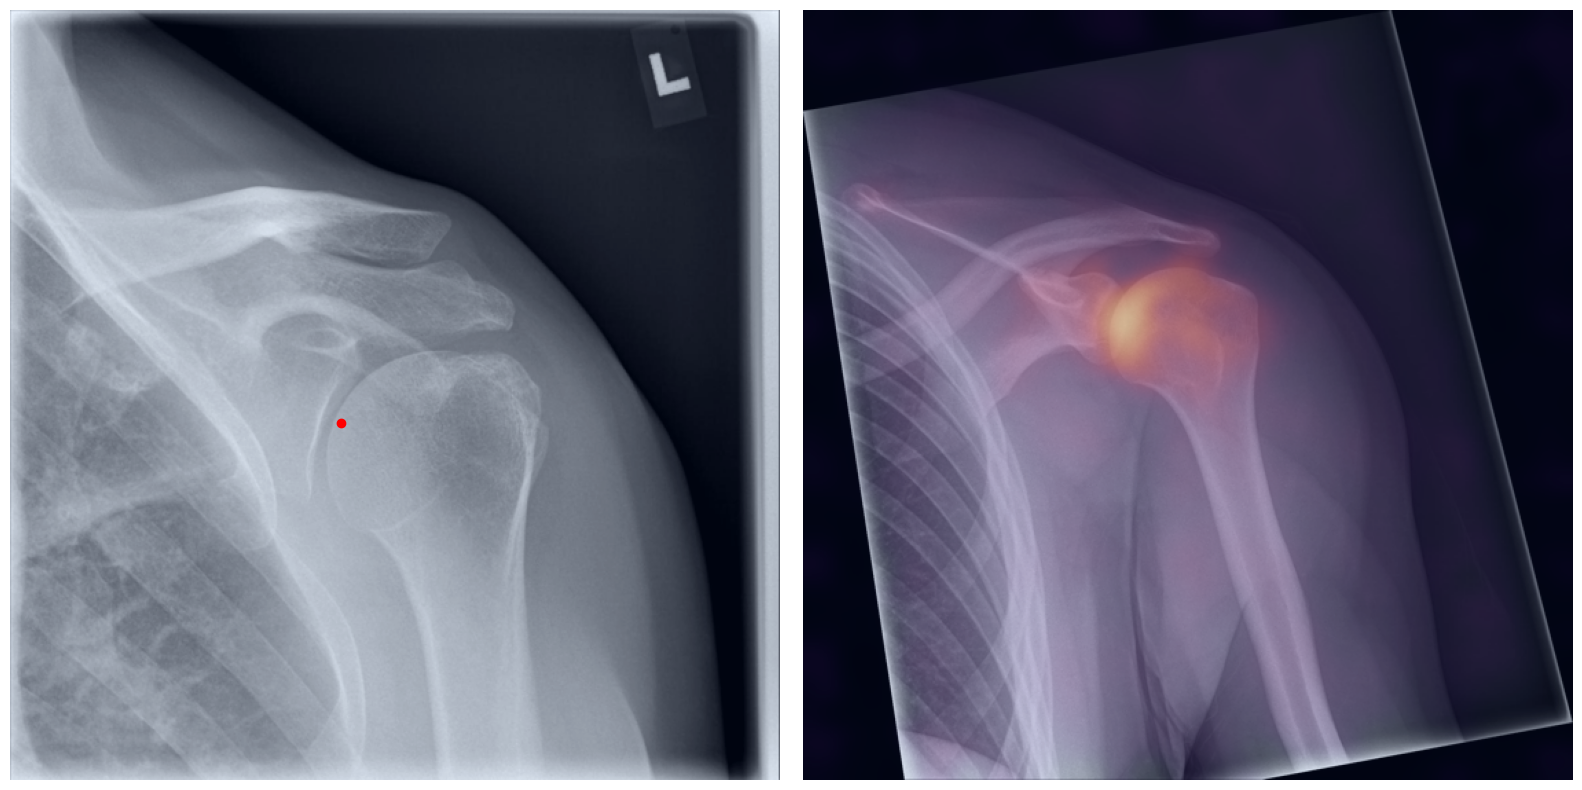

Artificial intelligence (AI) has shown great potential in assisting radiologists with musculoskeletal (MSK) assessments across various anatomical regions1,2,3,4. However, most existing tools are narrowly tailored for specific anatomies or rely on segmentation-based methods as a basis. To address these limitations, we propose a versatile and generalist AI-based approach for landmarks matching. In contrast to typical generalist landmark matching approaches that depend on automatically identified, optimally descriptive landmarks5,6,7, our use-case has to be based on manually selected landmarks tailored for MSK measurements. As these landmarks are potentially subotimal for precise matching, we employ an AI-based method8 that first performs multi-scale dense image matching between the reference and target images independently of the landmarks. The AI uses a combination of transformer and convolutional neural networks to establish a multi-resolution descriptive feature representation of each position within the images, allowing to define correspondences between the reference and target images. In a subsequent step, landmark positions are transferred to the target image based on these correspondences, with the determination of final locations benefiting from the redundancy of the dense matching. This enables robust automation of landmark matching from a reference patient across an entire cohort of target patients. The approach is anatomy-agnostic, enabling the use of the same backbone model for a wide range of anatomical regions and MSK measurements. For more detailed information we refer to our paper.

Once a correspondence between the reference and target radiographs is established, landmark matching can be performed in real-time. This process enables the alignment of individual points and allows for the definition of a predefined set of landmarks that can be mapped onto the target patient. These predefined landmarks can be customized for the automated calculation of specific measurements, which, once defined on a reference patient, can be consistently and automatically transferred to any radiograph within the target cohort.

The process of establishing a dense match between two images relies on abstract feature representations for each position in both the reference and target images. To better understand which information is encoded by the AI, we examined the feature similarities between a specific position within the reference image and the entire target image. Our findings show that the AI captures both semantic and texture features. The matching process utilizes this encoded information, along with precise positional data, to create a reliable mapping between the images.

From Novice to Expert: Annotation Through Imitation